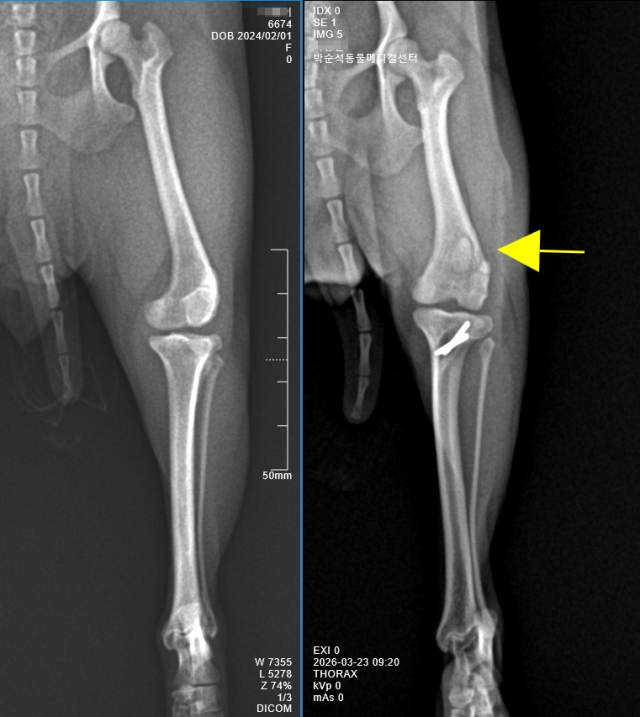

체중 3kg인 반려견의 슬개골탈구 수술 공간은 사람의 손가락 관절 정도에 비유될 정도다. 그 좁은 공간 내에서 활차구를 깍아내고, 경골결절을 자른 후 변위시켜 고정하는 섬세한 시술이 이루어진다. 이처럼 소형견을 대상으로 한 고도의 섬세한 시술들이 축적되면서, 국내 반려동물 수의학의 수준은 빠르게 발전해 왔다.

같은 '슬개골 탈구 수술'이라는 이름을 사용하더라도, 실제 적용되는 수술방법은 골의 변형정도, 골밀도 정도, 염증의 진행 여부 등을 고려하여 다양하게 적용되어 진다. 또한 수술 후 X-ray 검사에서 슬개골의 위치가 정상적으로 교정된 것으로 보이더라도, 임상적으로는 통증이 지속되는 경우가 적지 않다. 경우에 따라서는 퇴행성 관절염이 진행되며, 보행 장애와 만성 통증으로 인해 삶의 질이 저하되는 결과로 이어지기도 한다.

따라서 수술에 앞선 환자견의 정밀한 평가는 무엇보다 중요하다. 개체에 따라서는 수술 전 CT 검사가 필요한 경우도 적지 않다. 또한 골밀도가 충분하지 않은 경우에는 자가 골이식이 필요할 수 있으며, 슬개골 탈구로 내원했던 사례에서 실제로는 전방십자인대 손상이 동반된 경우도 빈번하게 확인된다.

그래서 슬개골 탈구 수술은 수술에 앞서 환자견에 대한 내과적 평가와 골밀도, 관절염, 십자인대 평가 등의 검사 과정을 거친다. 골변형 및 골질환이 염려된다면 CT 검사가 선행되기도 한다.